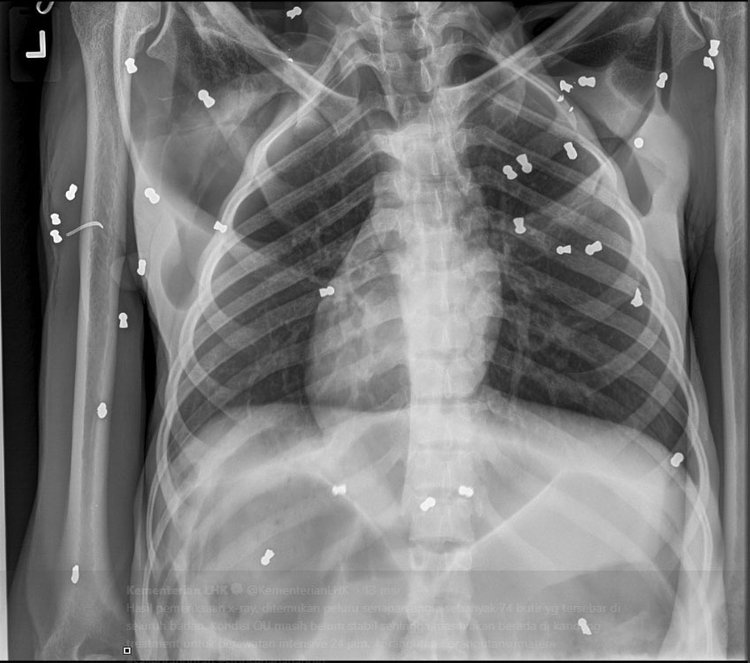

น่าเสียดายลูกลิงที่เรื่องที่อยู่ในสภาพย่ำแย่ได้เสียชีวิตระหว่างทาง และเมื่อทำการตรวจร่างกายแม่ลิงอย่างละเอียดก็พบว่าตลอดร่างกายของมันมีกระสุนตะกั่วที่ยิงจากปืนลม มากถึง 74 เม็ด ! แถมด้วยกระดูกที่หักเพราะถูกตีด้วยของแข็งหลายแห่งมาก แม้แต่ที่กระดูกคอก็หัก แต่มันไม่ตาย

ที่น่าสงสารมากก็คือ ตาของมันทั้งสองข้างมีกระสุนปืนยิงหลายนัดทำให้ตาบอดสนิท (เห็ดชัดในฟิล์ม)